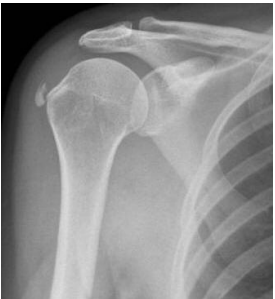

60 42 歲男性患者,從事室內裝潢工作,主訴反覆肩痛已三月餘,疼痛程度尚可忍受,但偶夜間痛醒, 外觀無明顯紅腫,經詢問無特殊運動傷害或明顯外傷史,經檢查 Hawkins impingement sign(霍金氏 夾擊現象)為陽性,X 光如圖所示。根據上述,初步可以診斷為何種疾病? (A)肩峰鎖骨關節骨刺 (B)三角肌勞損 (C)棘上肌鈣化 (D)肱骨大轉子骨裂